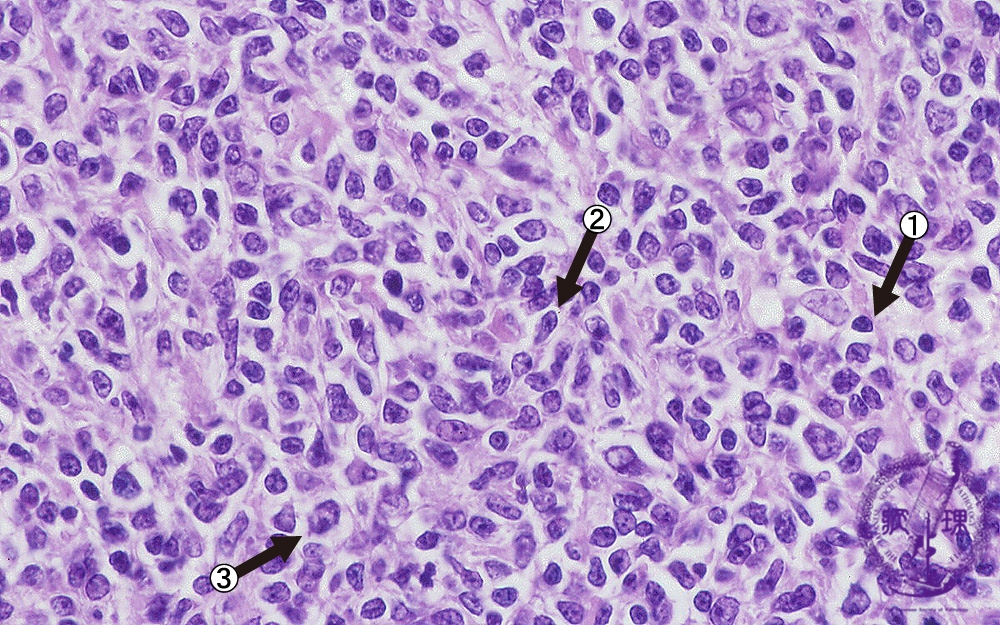

- ★(5)Follicular lymphoma

Microscopic image (H&E high power view): Nuclei of neoplastic lymphocytes are larger than those of mature lymphocytes (arrow No.1), but smaller than those of histiocytes. Some of the smaller tumor cells are called cleaved cells because their nuclei have irregular, notched borders (arrow No.2). Admixed centroblasts (arrow No.3) are larger tumor cells with prominent large nucleoli. The germinal center growth pattern is relatively monotonous in contrast to the heterologous appearance seen in non-neoplastic, reactive areas.